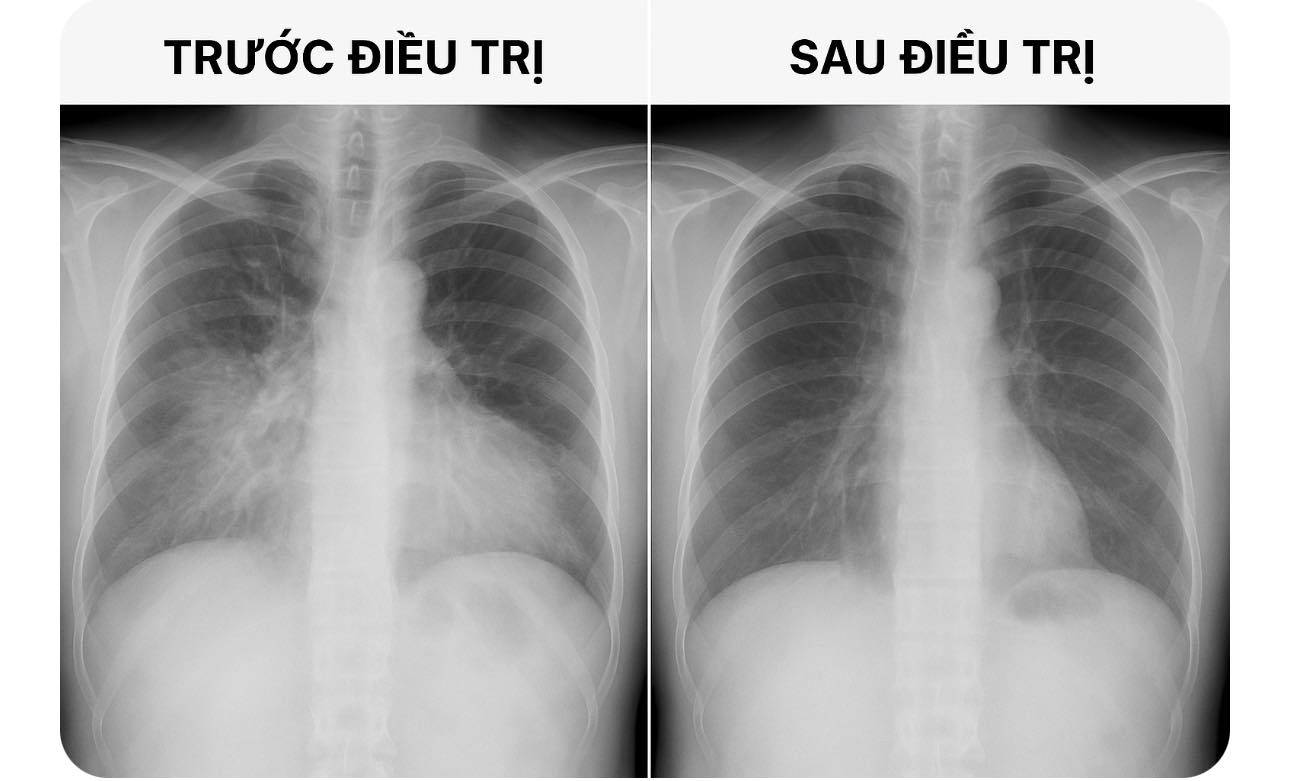

So sánh hình ảnh X-quang phổi viêm phổi trước và sau điều trị, giúp nhận biết hiệu quả điều trị và tình trạng hồi phục của nhu mô phổi:

Trước điều trị: Hình mờ phế nang đồng nhất vùng thùy dưới phổi phải, có dấu hiệu phế quản hơi, giới hạn không rõ, gợi ý viêm phổi thùy dưới phải cấp.

Sau điều trị: Hình mờ phế nang vùng thùy dưới phổi phải giảm rõ, phổi sáng trở lại, không còn dấu hiệu thâm nhiễm – gợi đáp ứng điều trị tốt.

3. So sánh trực tiếp:

Tiêu chí Trước điều trị Sau điều trị

Mức độ mờ phổi Mờ đậm, lan tỏa hoặc khu trú Giảm mờ hoặc sạch hoàn toàn

Dấu phế quản hơi Thường có Mất

Rốn phổi Đậm, dày Bình thường

Dịch màng phổi Có thể có Hết

Thông khí phổi Giảm Cải thiện

Cấu trúc phổi Mất chi tiết mạch máu Rõ lại bình thường